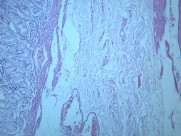

慢性萎缩性胃炎大全(12)张

本病以胃粘膜萎缩变薄,粘膜腺体减少或消失,并伴有肠上皮化生,固有膜内多量淋巴细胞、浆细胞浸润为特点。本性胃炎的病因比较复杂,部分可能与吸烟酗酒和用药不量有关,部分由慢性浅表性胃炎迁移发展而来,还有部分属兔自身免疫疾病。